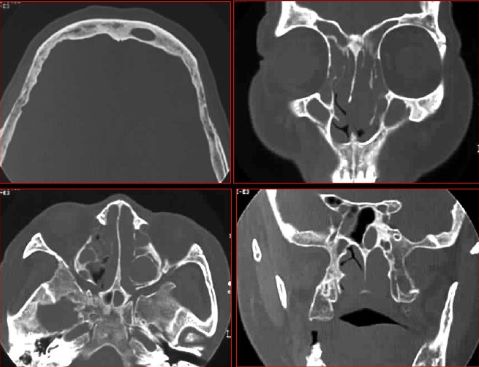

急性鼻窦炎

平片及CT检查表现

Water氏位:窦腔混浊,液平面

CT:

鼻窦密度增高

骨壁破坏

脓肿

并发症